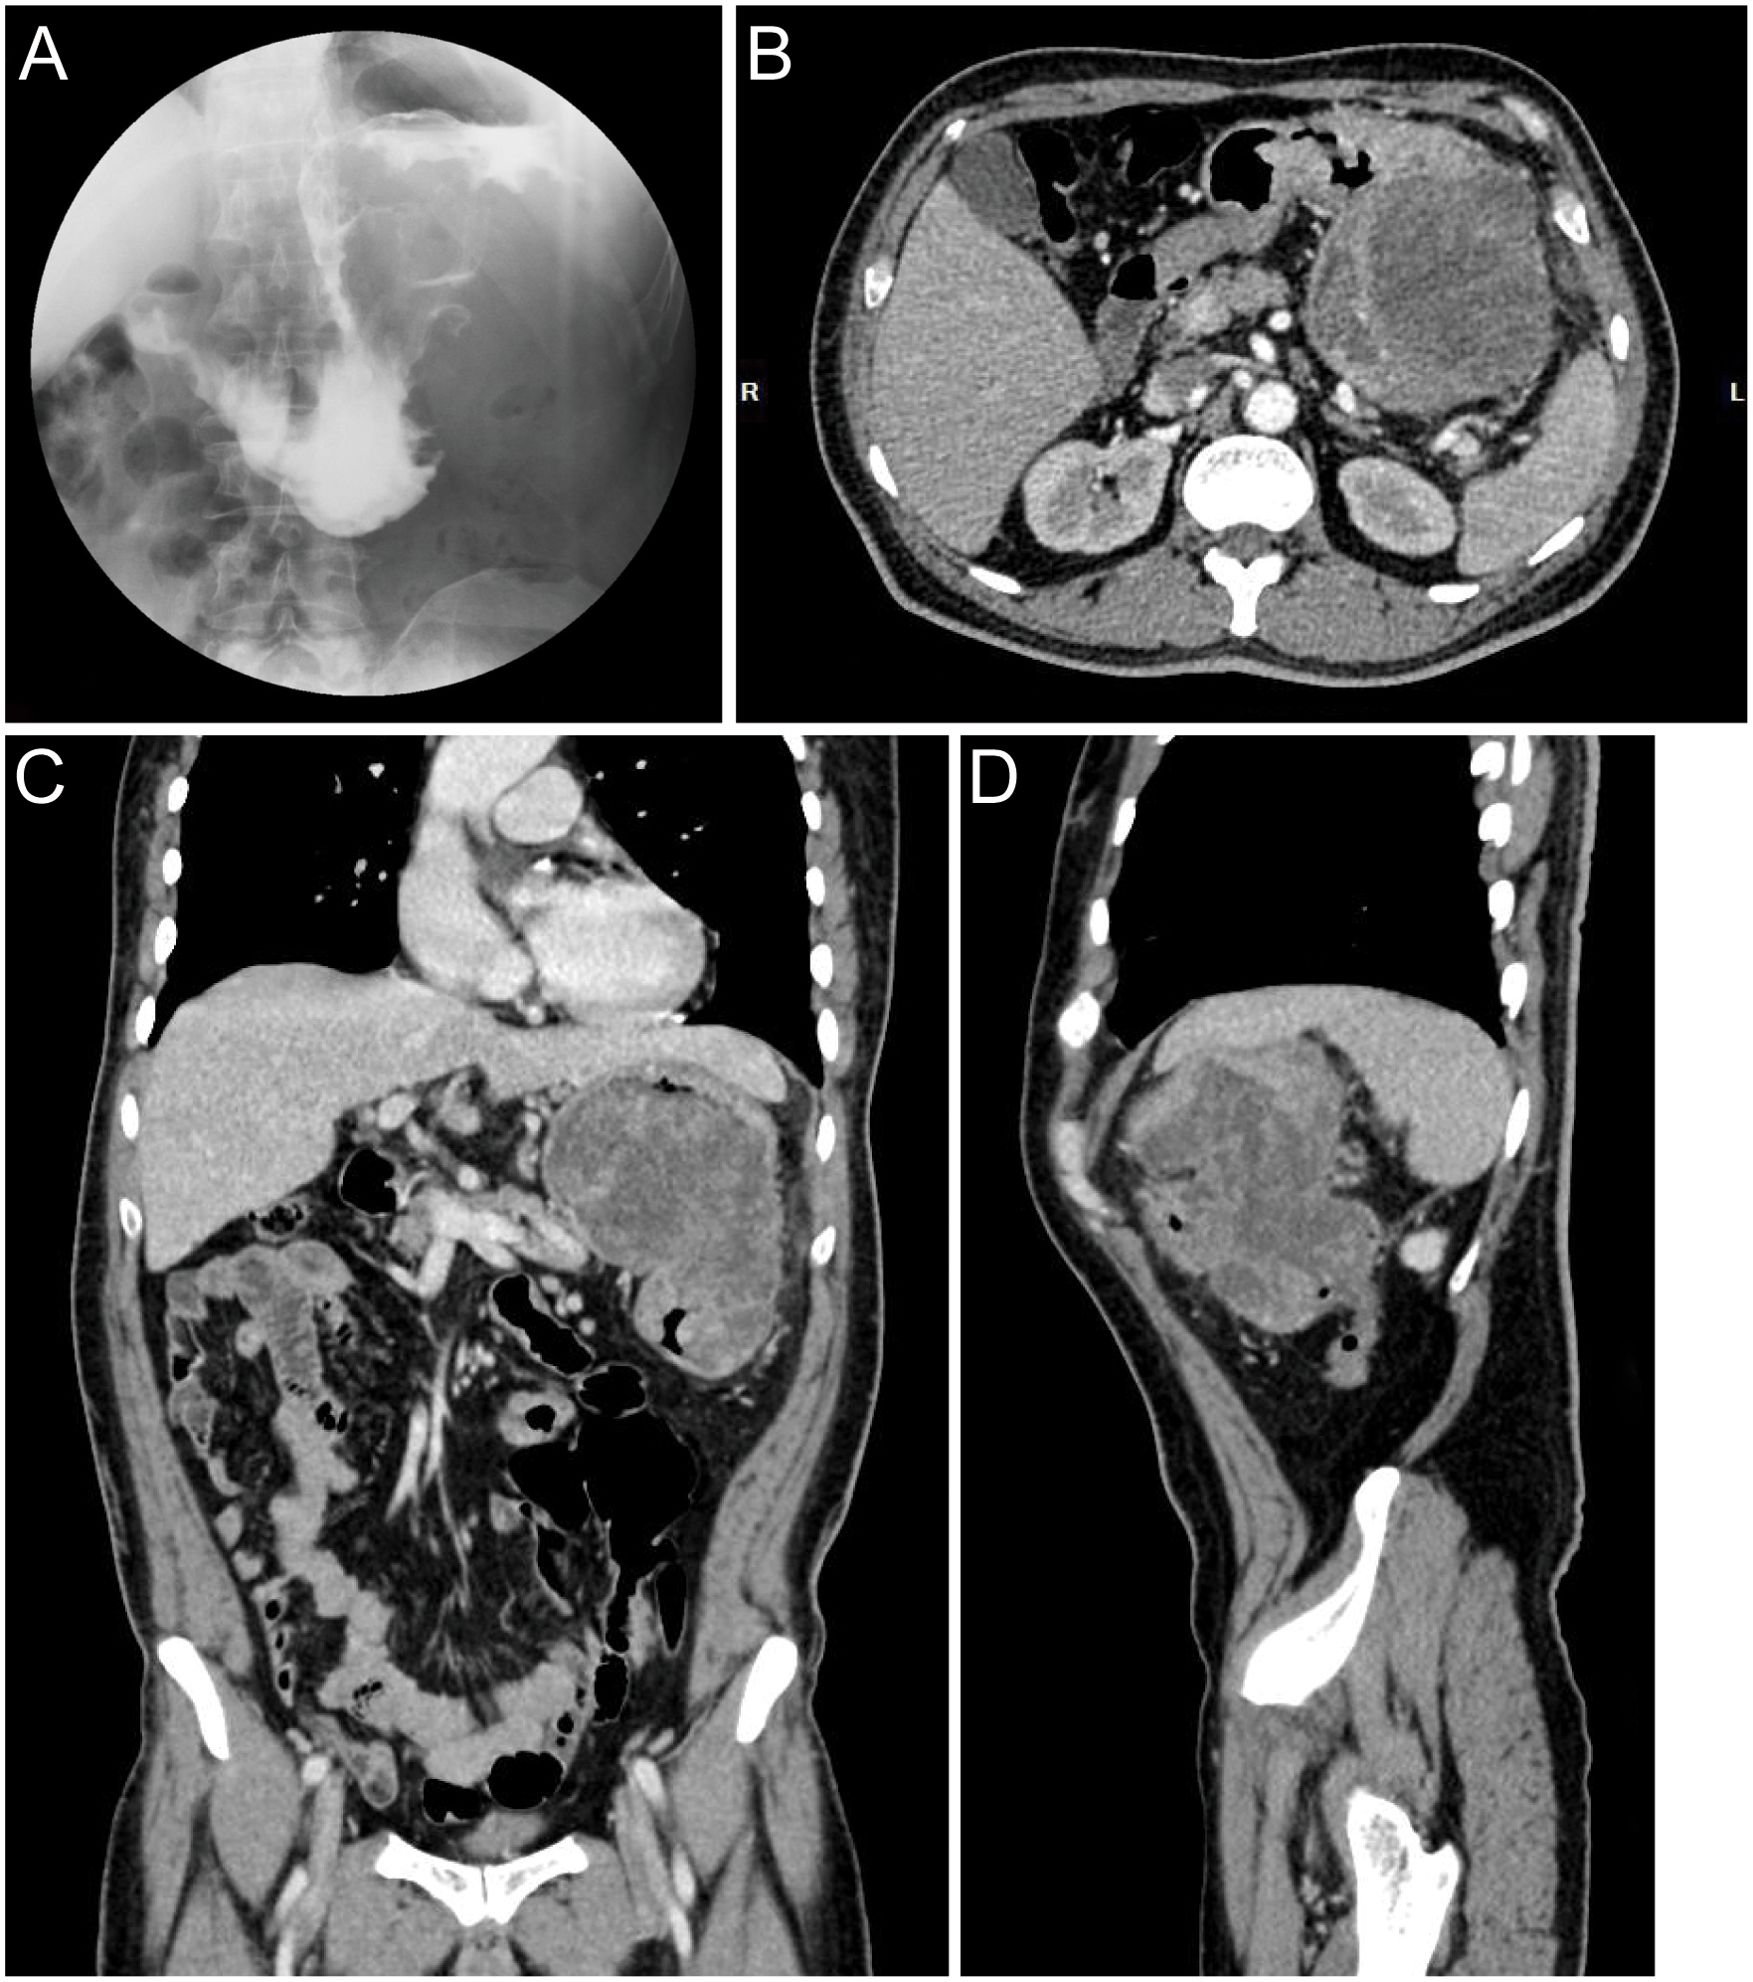

A 60-year-old male presented with a 30-day history of melena and progressive fatigue without hematemesis, nausea, or abdominal distension. Physical examination revealed marked pallor, and laboratory testing confirmed severe anemia (hemoglobin 64 g/L). Initial contrast-enhanced abdominal CT at a local hospital demonstrated a huge hypodense intragastric mass. Following referral to a tertiary center, repeat CT identified an exophytic gastric lesion with multiple perigastric lymph nodes (Figure 1). Upper endoscopy revealed a giant irregular protrusion occupying the entire gastric body along the greater curvature (Figures 2A, B). Biopsies showed high-grade intraepithelial neoplasia with focal carcinomatous transformation, with Helicobacter pylori immunohistochemistry (IHC) negative. A provisional diagnosis of gastric adenocarcinoma was established, and radical gastrectomy was planned.

Figure 1

Four medical imaging scans are displayed. Image A shows a frontal fluoroscopy view of the abdomen. Image B is an axial CT scan of the abdomen, revealing internal structures. Image C is a coronal CT scan, offering a vertical view of the abdomen. Image D is a sagittal CT scan, providing a side view.

Figure 1. Preoperative radiographic images. (A) Upper GI series with barium contrast showing a large filling defect in the greater curvature gastric wall. Axial (B), coronal (C), and sagittal (D) contrast-enhanced CT images documenting a large mass contiguous with the gastric body.